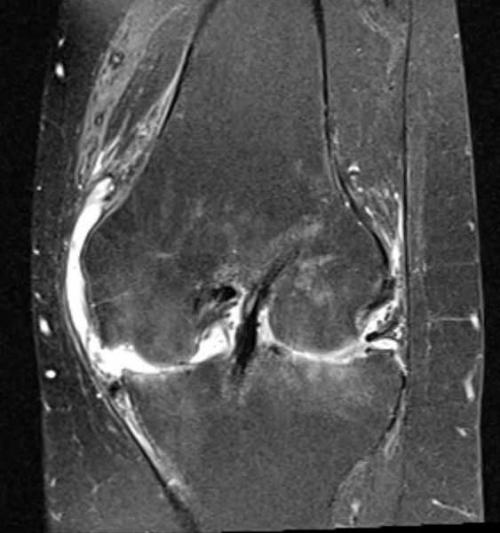

Актуальность. Оценка анатомического строения коленного сустава имеет большое практическое значение, так как часто возникают трудности в решении вопроса о норме и патологии. Методы лучевой диагностики являются основными для определения патологий коленного сустава.Цель исследования. Провести сравнительный анализ современных лучевых методов при оценке анатомических структур коленного сустава.Материал и методы исследования. Проведен анализ теневых изображений коленного сустава подростка 18 лет, полученных при исследовании в Клинической больнице им. С.Р. Миротворцева СГМУ. Методы исследования: рентгенография (РГ) в прямой и боковой проекциях на рентгеновском аппарате с цифровой техникой, ультразвуковое исследование ( УЗИ ) с допплерографией, компьютерная томография (РКТ), магнитно-резонансная томография ( МРТ ).Результаты. Рентгеновский снимок показывает только костные изменения. Рентгеновские лучи поглощаются плотной костной тканью благодаря содержанию кальция. А анатомические особенности колена таковы, что чаще всего повреждения имеют как раз связочно-менисковые структуры. Компьютерная томография дает изолированное изображение поперечного слоя тканей, которое невозможно получить при обычной рентгенодиагностике. В отличие от других диагностических методов, МРТ дает возможность визуализации не только костных структур и хрящевых тканей суставов, но и окружающих мягких тканей. У ультразвукового исследования есть несколько важных особенностей: 1 – результат во многом зависит от качества аппаратуры, которая обеспечивает наибольшую четкость изображения и его детализацию; 2 – высокий профессионализм врача, который способен увидеть даже признаки только еще зарождающейся патологии.Заключение. Анализ результатов лучевых методов исследования коленного сустава, проведённых у одного и того же пациента на одном и том же суставе показал следующее: при оценке состояния анатомических структур коленного сустава методом первой очереди остается РГ, поскольку позволяет увидеть структуру костей и косвенно судить о состоянии менисков. В случаях подозрения на наличие суставной жидкости в суставе рекомендуется УЗИ . При трудностях определения патологии в суставе методами РГ и УЗИ , а также для уточнения состояния его костных структур рекомендуется КТ , а при подозрении на повреждение связочного аппарата МРТ .

Магнитно-резонансная томография или МРТ коленного сустава – современная, безопасная, неинвазивная диагностическая процедура, позволяющая с высочайшей точностью визуализировать мягкотканные структуры (мениск, связки, сухожилия, кровеносные сосуды, мышцы) и выявить малейшие изменения в них. С несколько меньшей информативностью она помогает обнаруживать повреждения костной ткани разного типа, но правильно расшифровать, что показывает МРТ коленного сустава, может только квалифицированный врач-рентгенолог.

МРТ коленного сустава современная, безопасная, неинвазивная диагностическая процедура, позволяющая с высочайшей точностью визуализировать мягкотканные структуры (мениск, связки, сухожилия, кровеносные сосуды, мышцы) и выявить малейшие изменения в них.

Метод помогает обнаружить различные заболевания коленного сустава и околосуставных тканей даже на самых ранних стадиях развития. Томография показывает малейшие отклонения от нормы и позволяет определить следующие нарушения:

- воспалительные болезни (артрит любого вида, остеомиелит, бурсит, тендинит, инсерциит, тендовагинит, эпикондилит, лигаментит и пр.);

- невоспалительные дегенеративно-дистрофические заболевания (артроз, болезнь Кенинга, Осгуда-Шлаттера, синовиальный остеохондроматоз, гидрартроз, хондропатию надколенника);

- системные заболевания и их следствия (подагру);

- анатомические аномалии;

- различные разновидности травматических повреждений (растяжения, разрывы связок и сухожилий, трещины и переломы костей, отрывы хрящевых фрагментов);

- опухоли доброкачественной или злокачественной природы, включая кисту Бейкера, синовиому, метастазы;

- защемление нервов.